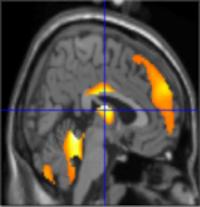

Magnetic Resonance Imaging

The brain MRI of a young patient reveals MS-like lesions in this individual with a fully positive IgG Lyme Western blot, indicating immune reactivity against the agent of Lyme disease.

Unlike SPECT and PET images which assess brain function, MRI captures the physical structure of the brain. Inflammatory abnormalities in the brain are also assessed with MRI scans. In children with neurologic Lyme disease, the MRI may reveal white matter hyperintensities suggestive of inflammation or areas of demyelination. Up to 40% of adults with Lyme disease may also have small white matter hyperintensities, but it should be noted that the number of hyperintensities increase with age — even among patients who do not have Lyme disease. In addition, certain factors such as ischemic disease or a history of smoking may result in an increased number of hyperintense areas.

The white matter hyperintensities are sometimes called UBOs or "unidentified bright objects". In some patients, antibiotic treatment results in a diminution or disappearance of these hyperintensities. Certain MRI sequences, such as FLAIR, are best able to detect hyperintensities. These MRI images in Lyme disease may appear similar to the demyelinated areas seen in the "white matter" of the brain MRI of patients with multiple sclerosis. Because an MRI scan uses a very powerful magnet, patients with pacemakers or other metallic implants should not get an MRI.